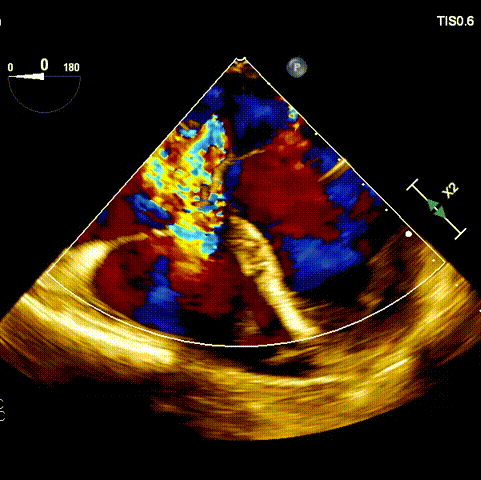

術前超聲

接受手術的為一名80歲男性,因“心悸2年,氣喘伴下肢水腫半年”入院。超聲心動提示“極重度三尖瓣反流,右房及右室明顯擴大,右心收縮功能輕度減低,左心收縮功能正常,肺動脈壓力正常”。患者同時合并有“持續性房顫”及“慢性心力衰竭”,病史持續2年,規律口服抗凝及強心、利尿治療治療效果不佳,癥狀持續。經廈心心臟團隊評估后,認為患者三尖瓣極重度反流并伴有心衰表現,長期內科藥物治療效果不佳,且患者高齡、外科手術風險高,因此決定采用微創經頸靜脈LuX-Valve Plus三尖瓣置換系統為患者治療。